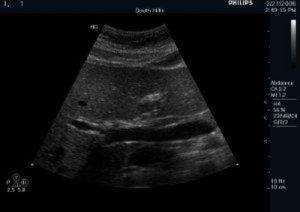

Learn to perform a comprehensive liver Doppler examination with this course, focusing on assessing the portal circulation, liver vasculature, and common liver diseases like cirrhosis and portal hypertension. Master Doppler techniques for evaluating portal veins, hepatic veins, and arteries, and understand how to identify vascular abnormalities and complications.

Appreciate proper liver duplex examination techniques and interpretation

Identify ultrasound findings associated with liver disease